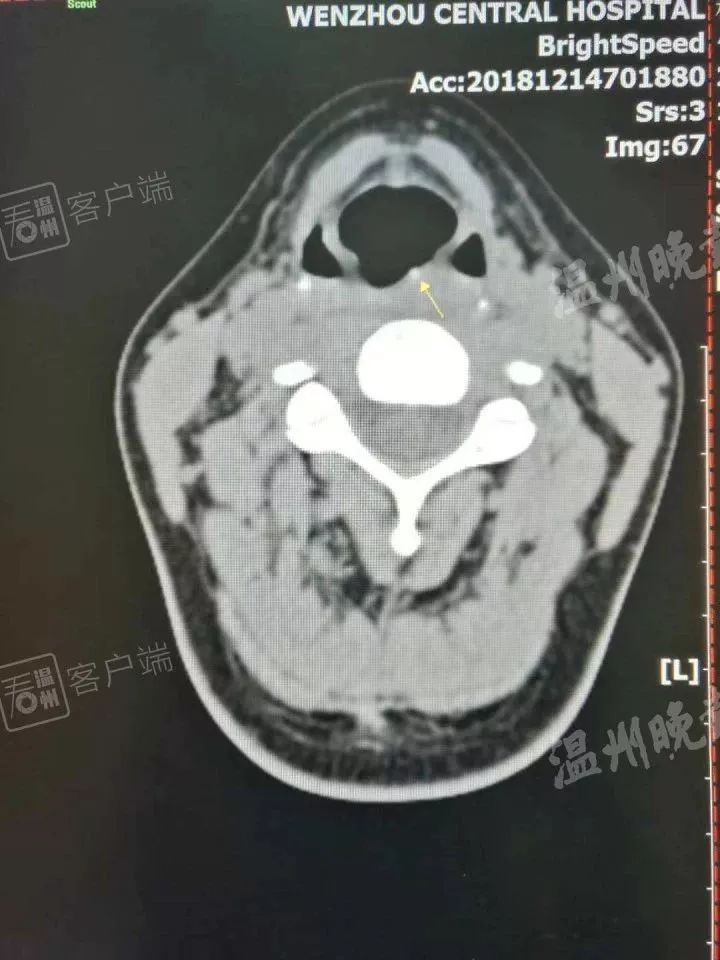

接诊的是该院耳鼻喉科医师伍淦。伍淦说,他用间接喉镜检查了一遍,也没有发现异物卡喉,后来让杨女士做了CT,这才找到刺入咽后壁(大约喉结位置)里的“暗器”。“患者必须发‘E’的音,才能通过喉镜看到‘暗器’露出的尖尖角。只要看到了,很快就取出来了。”